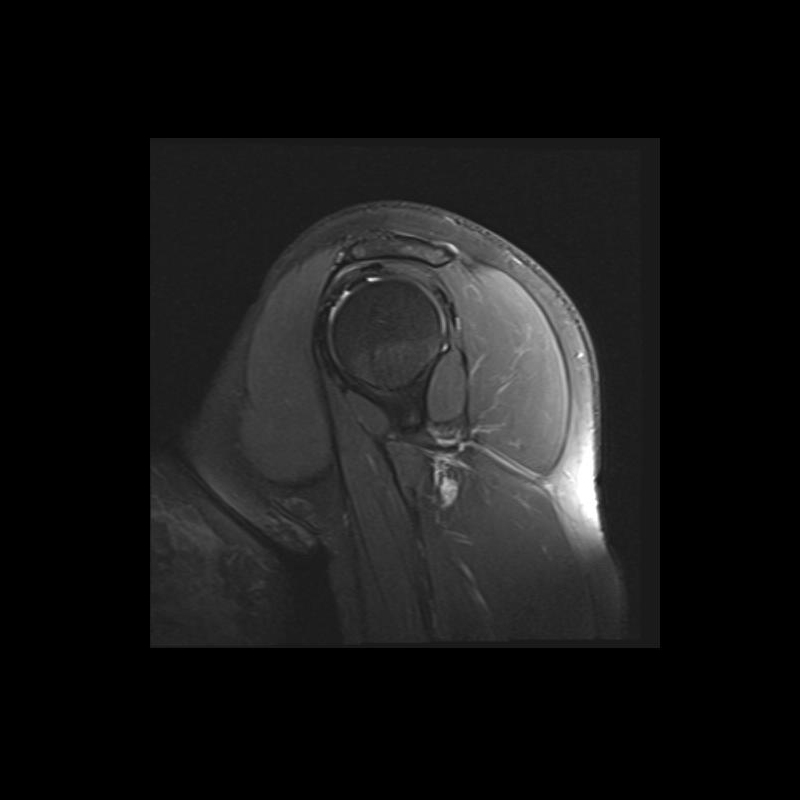

Shoulder MRI Anatomy